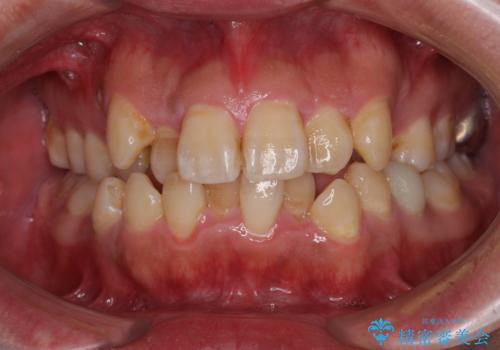

目立たない装置でデコボコを改善 ハーフリンガルによる矯正治療

- 上下顎歯列のデコボコを改善したいとのことで来院された患者様です。

自己管理の大変なインビザラインや、目立つ表側のワイヤー矯正は避けたいとのことで、

上顎だけ裏側装置のハーフリンガルにて矯正しました。

一年と数か月で矯正を終えることができました。

下顎前歯部には後戻り防止のワイヤーを装着しています。